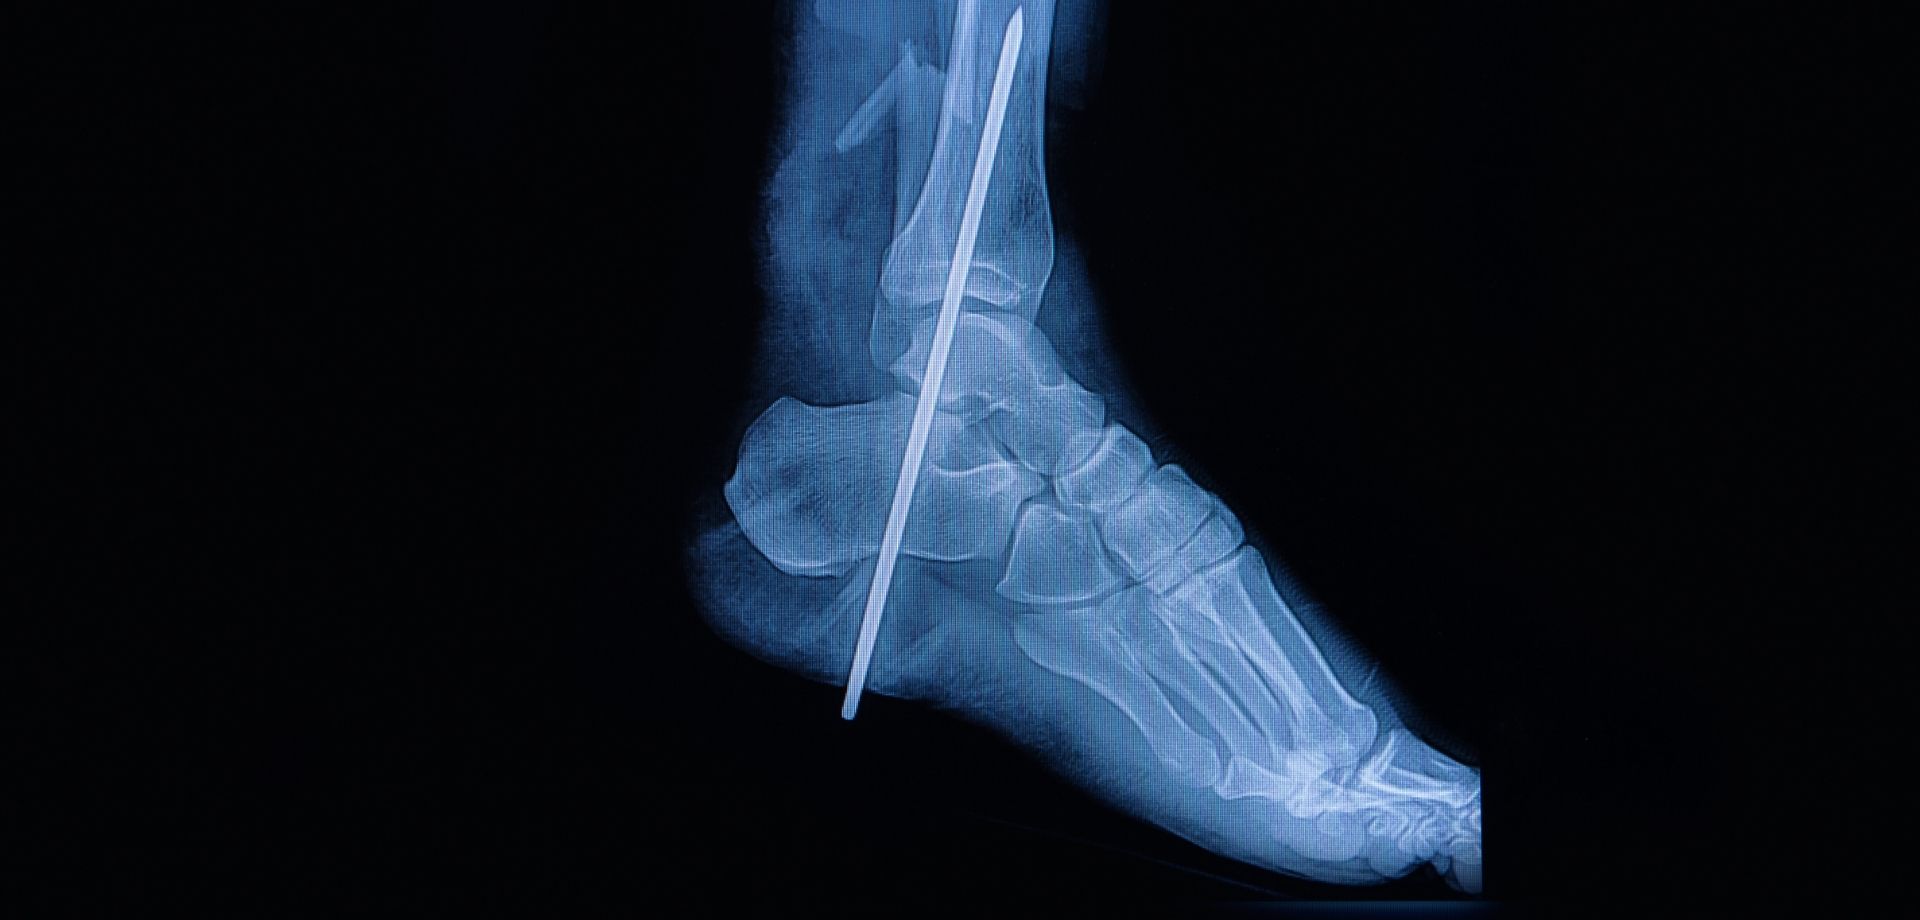

The department offers a full spectrum of non-surgical and surgical orthopedic services, with a strong emphasis on minimally invasive techniques. Advanced procedures such as arthroscopy, minimally invasive and endoscopic spine interventions, and modern fracture fixation methods are used to reduce surgical trauma, minimize pain, and promote faster recovery with shorter hospital stays. These approaches allow patients to return to daily activities and work more quickly, while maintaining high standards of safety and clinical outcomes.

- Sports Fractures

- Osteoporosis-Related Fractures